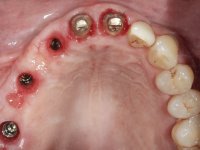

The patient was proposed to undergo a fixed oral rehabilitation consisting of a 2-element bridge over teeth 11 and 21 and a 5-element bridge over 3 implants that would be placed in the location of teeth 22, 24 and 26. The prosthetic structures would have an infrastructure in Zr coated with ceramic and the bridge over the implants would be screwed. The indicated extraction of teeth 25 and 26 and placement of an implant in the 26 site would imply surgery to fill the maxillary sinus. As the patient showed interest in having fixed temporary rehabilitation during treatment, we divided the treatment into 6 phases to achieve this goal: 1- Placement of a temporary bridge over teeth 11,21,25 and 26. With tooth extraction 24. 2- Placement of 2 implants in the location of teeth 22 and 24. 3- Placement of a temporary 6-element bridge over teeth 11 and 21 and over the implants. 4- Carrying out surgery to fill the maxillary sinus. 5 – Placement of the implant in the location of tooth 26 and in the area where the filling of the maxillary sinus was made. 6 – Placement of the definitive work.

A temporary acrylic bridge made in the laboratory with 7 elements was made, with teeth 11,21, 25 and 26 as pillars. The old bridge was removed and tooth 24 was extracted. The provisional bridge after relining was cemented in the mouth. Two implants were placed in the teeth 22 and 24 and 3 months after this intervention an impression was made to make a temporary bridge screwed over the implants and cemented to the teeth. The bridge was placed in the mouth and teeth 25 and 26 were extracted. 3 months later, surgery was performed to fill the maxillary sinus and 6 months later the implant was placed in the location of tooth 26. After osseointegration of this implant, the final impression was made for the final work. The bridge over the implants was permanently screwed on and the bridge over the teeth was cemented with resin-reinforced glass ionomer cement.